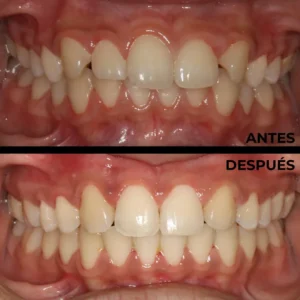

En clínica dental María Jiménez somos especialistas en ortodoncias, siendo la especialidad que se encarga del correcto posicionamiento de los dientes en la boca, para una óptima función masticatoria, fonética y estética, evitando muchos problemas debidos al apiñamiento y mal posición de los dientes.

Tener los dientes alineados y una buena oclusión generan un buen estado de salud bucal y evita problemas en el futuro además de una estética y una sonrisa más atractiva. Las mal oclusiones afectan el estado de la boca, pero además causan otros problemas dentales como desgastes en los dientes, problemas de encías, fracturas, y dificultad muchas veces para poder llevar una buena higiene dental.

Con los tratamientos de ortodoncia conseguimos muchos beneficios a nivel de higiene, estética, salud dental y evitamos futuros problemas funcionales, mejoramos muchas veces la autoestima de los adolescentes y la salud bucal en general.